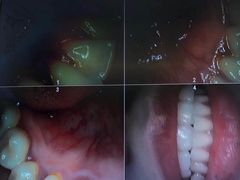

• 牙博士口腔品牌连锁(杨浦店)

• -牙博士口腔品牌连锁(杨浦店)

sddstan07 | 20-10-28